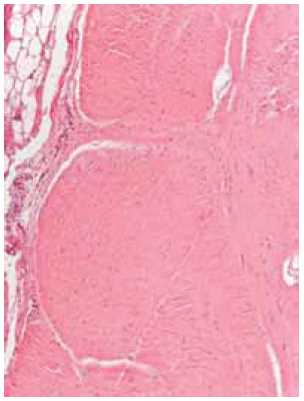

Morphological study. The excised part of the cord (12.5 × 1.8 × 1.0 cm) was represented mainly by a uniformly stained whitish tissue. After primary fixation in a 10% solution of neutral formalin, several blocks were cut, and after processing using 10 baths with isopropyl alcohol followed by paraffin embedding, 4-μm-thick sections were cut using a rotary microtome (Thermo Scientific, Microm HM 340 E). The histological sections were dewaxed using xylol then stained with either hematoxylin and eosin or Van Gieson’s stain.

Histological preparations were examined using a light microscope (AXIo Scope A1, ZEISS) with polarized light. Sections of fragments of dense fibrous tissue were observed, with structures reminiscent of tendon tissue, but weakly vascularized and partially teased in places. Bunches of collagen fibers of different thicknesses were arranged in parallel and were oriented predominantly in one direction (Fig. 7).

Fig. 7. Longitudinal sections of an area of weakly vascularized fibrous cord. Unidirected bundles of collagen fibers with a relatively small amount of several unevenly distributed fibrocytes (a). Staining with hematoxylin and eosin and Van Gieson’s stain (b). Magnification × 300

The fibrous cord tissue there showed a relatively small amount of several unevenly distributed connective tissue cells (fibrocytes).

Some areas on the surface of the cord showed “remnants” of a thin fibrous “tunic” with occasional single small cells of differentiated fatty tissue, along with single adipocytes, also found in the individual fields of vision in the fibrous cord tissue itself (Fig. 8).

Fig. 8. Tangential section of an area of fibrous cord with well-distinguishable bundles of collagen fibers and a relatively small number of fibrocytes. On the edge of the cord there is a visible part of a thin fibrous “tunic” with a fragment of a cell of differentiated fatty tissue (staining with hematoxylin and eosin, magnification × 300)

Some heterogeneity of the structure was noted near the partially teased areas. Narrower layers of slightly more vascularized fibrous tissue, formed by thin, chaotically oriented collagen fibers were wedged between parallel-oriented bundles of relatively thick collagen fibers (Fig. 9).

There were no signs of tumor growth (benign or malignant) or inflammatory changes in the sections studied.